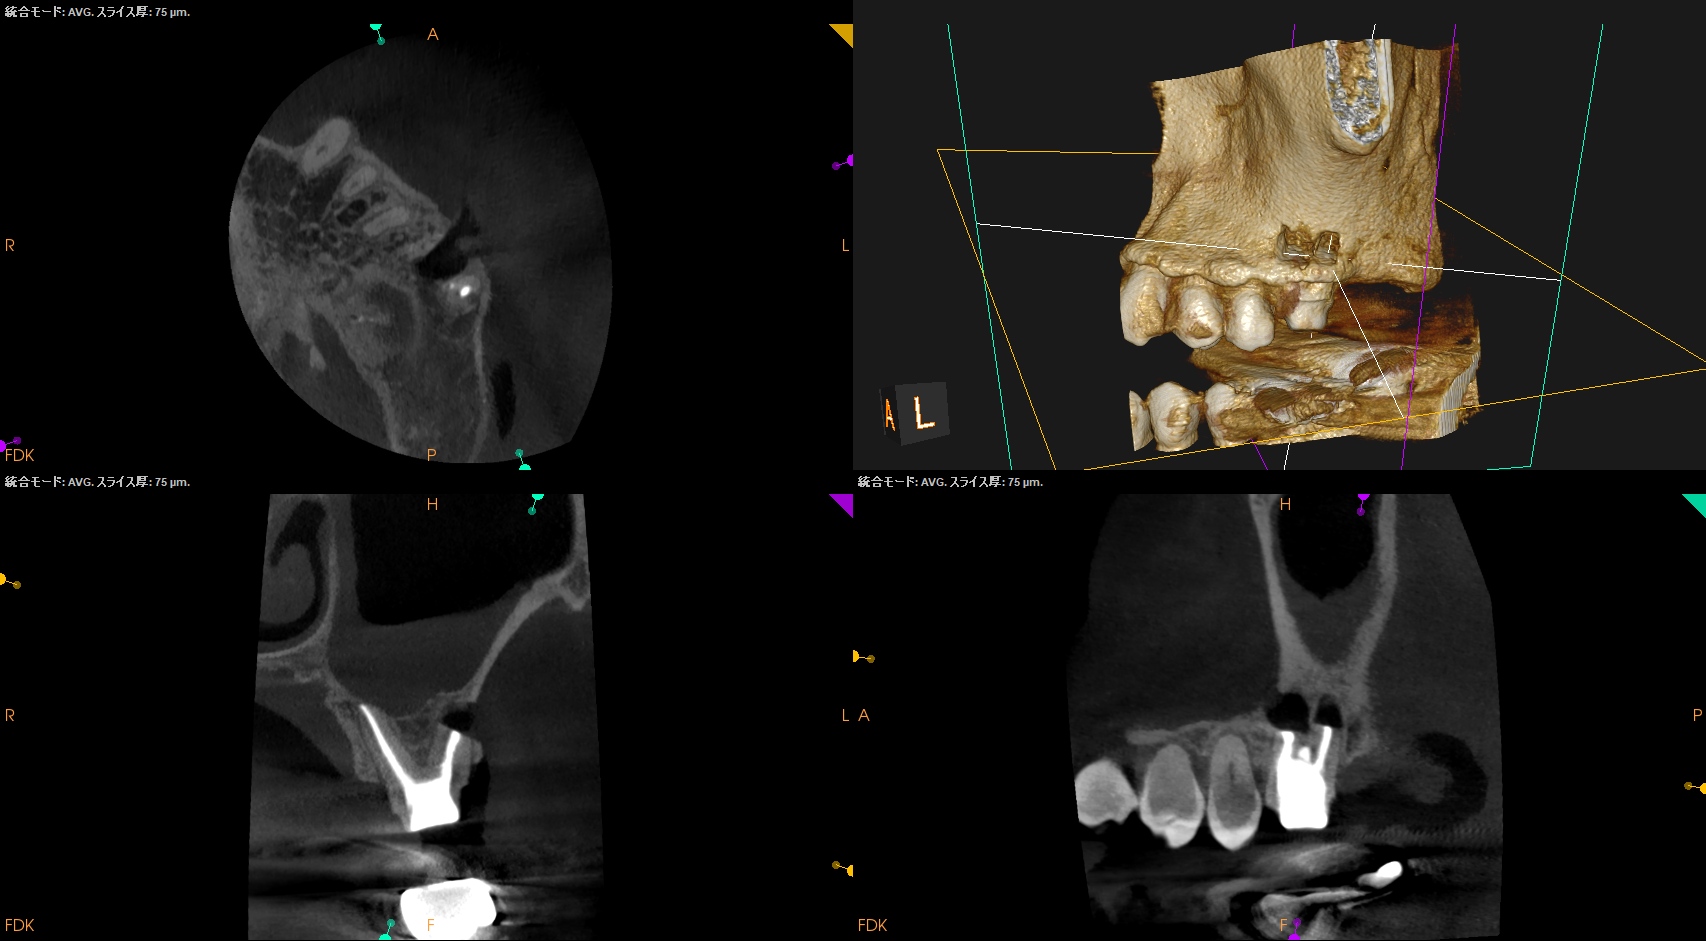

#14 RCT 2yr recall(2026.1.21)

MB,DBの根尖部に病変が残存している。

臨床検査での咬合痛が生活に支障があるそうだ。

#14 MB,DB Apicoectomyが必要である。